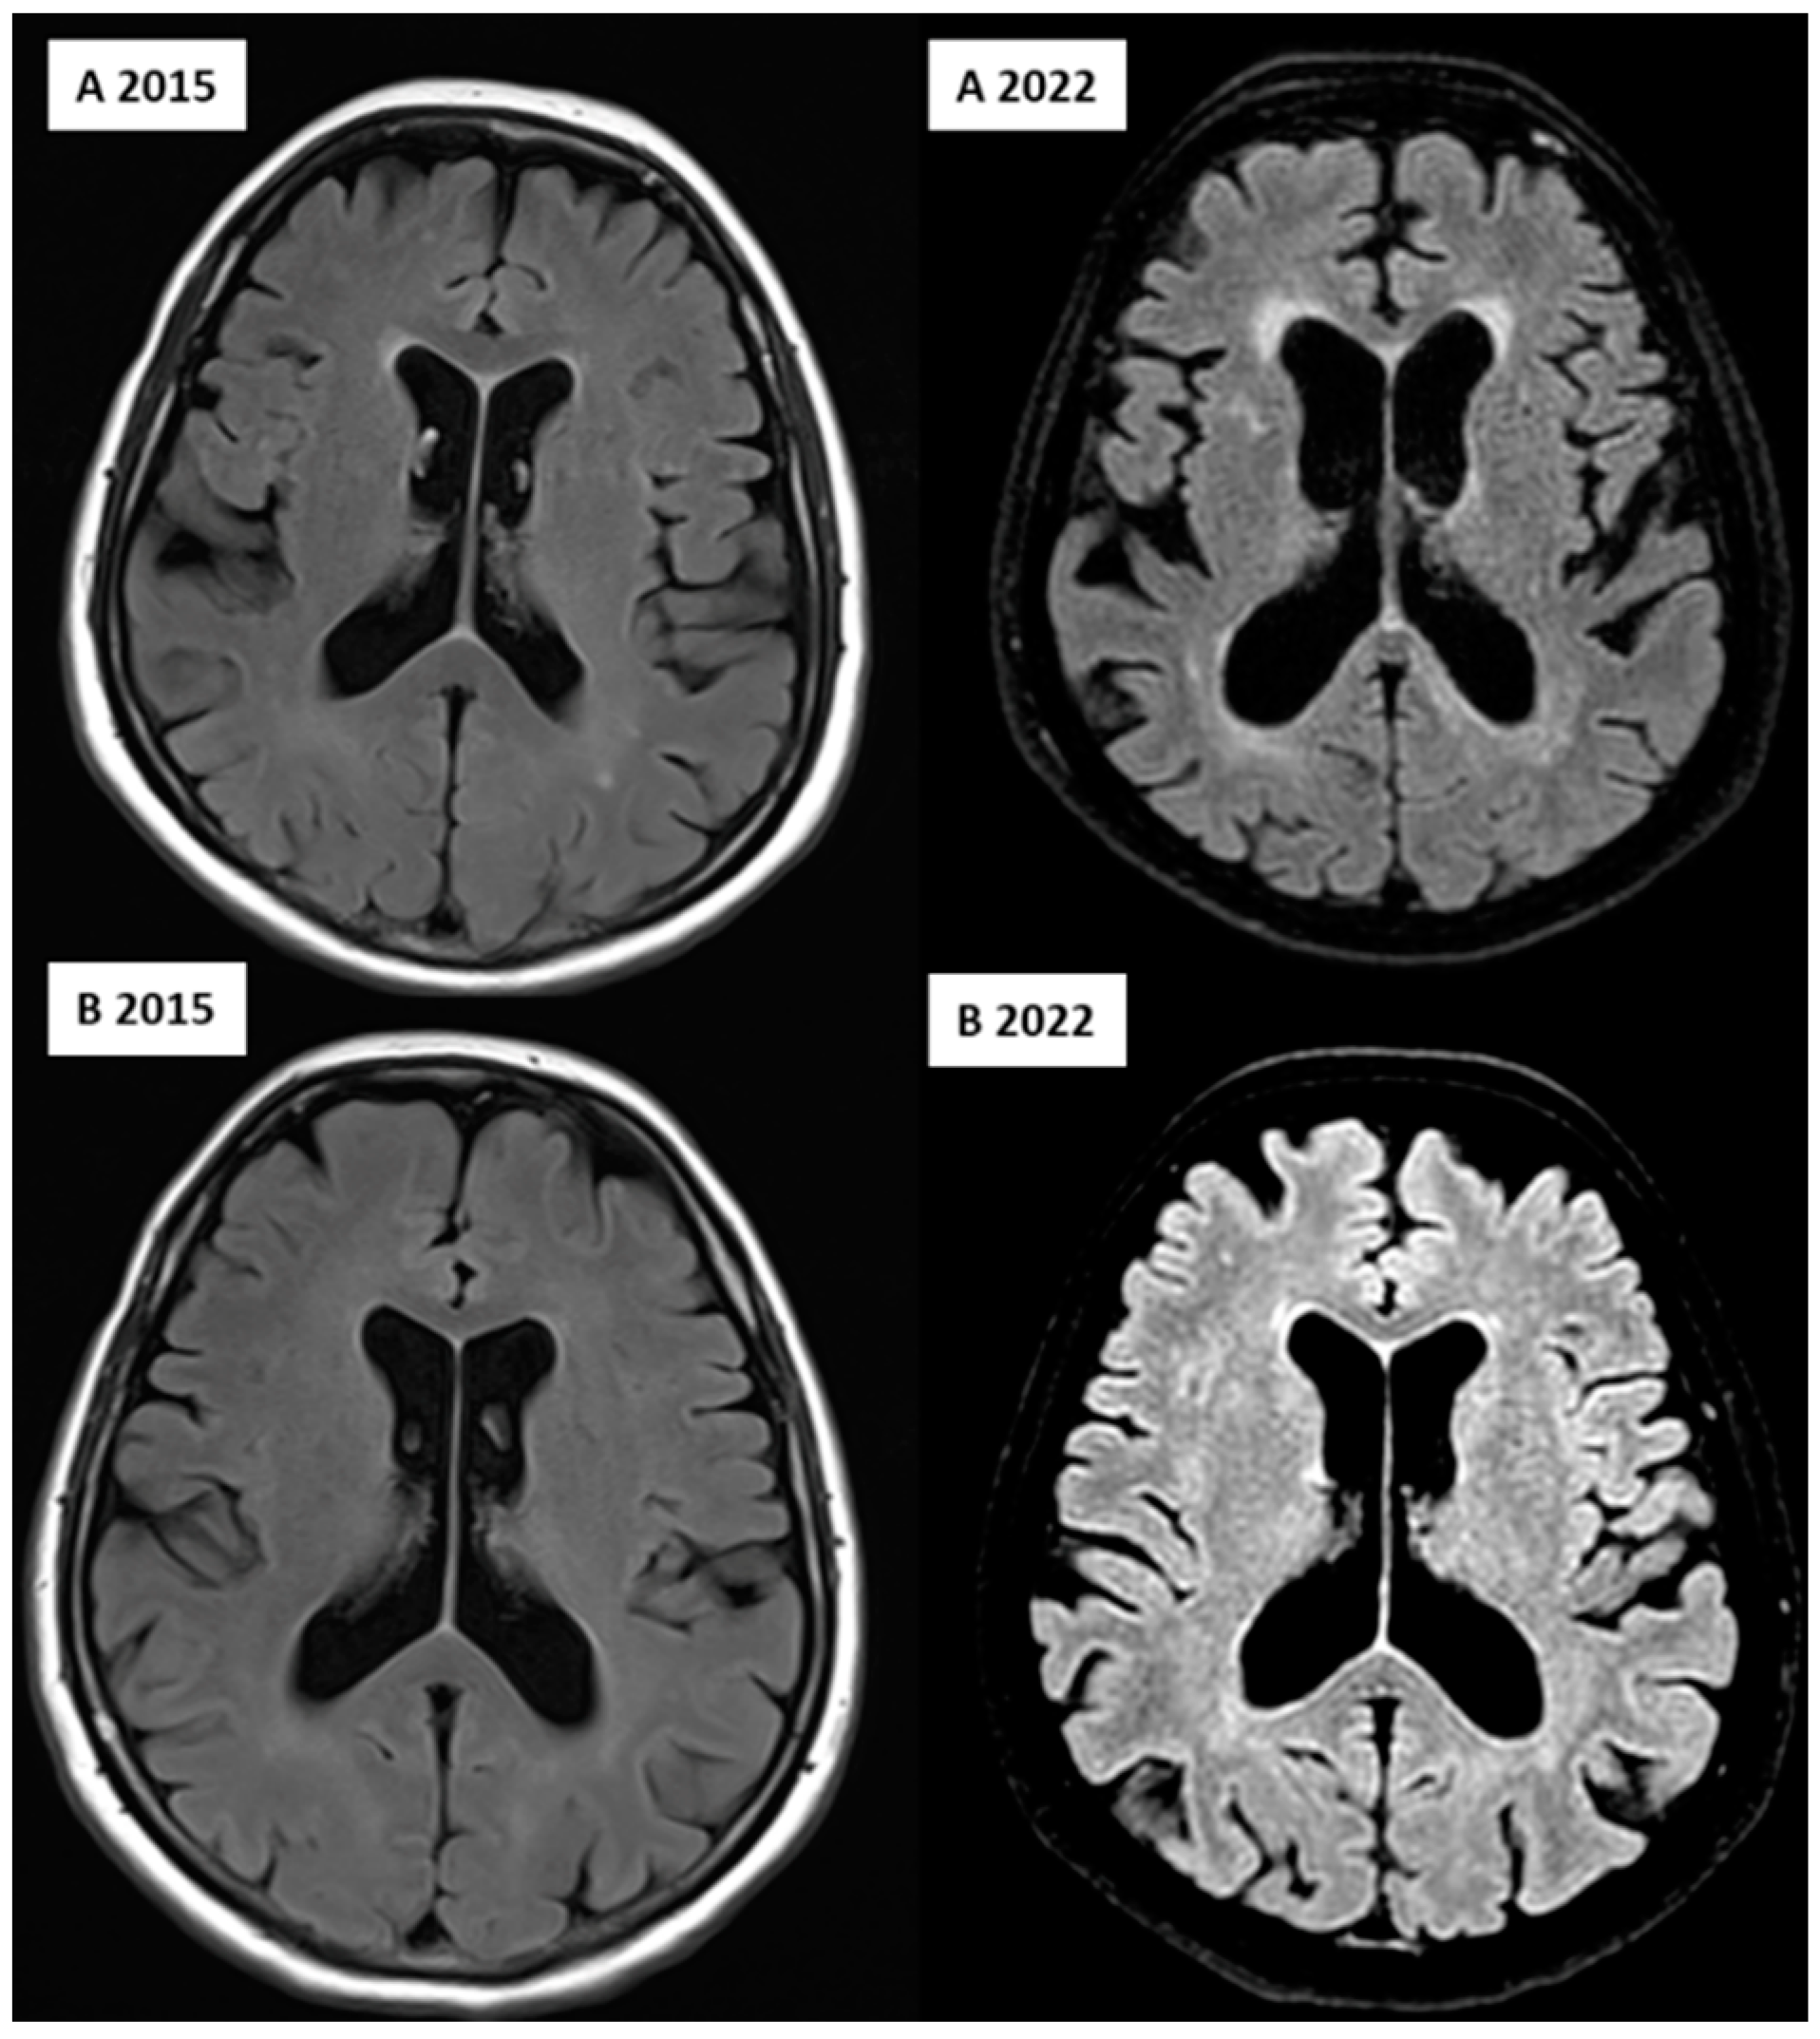

| Variable | Unaffected Twin | Affected Twin |

|---|---|---|

| Total lesions count | 24 | 36 |

| Total lesions volume (cm3) | 3.9192 | 30.0650 |

| Periventricular lesions count | 9 | 8 |

| Periventricular lesions volume (cm3) | 3.3902 | 29.4052 |

| Deep white lesions count | 12 | 17 |

| Deep white lesions volume (cm3) | 0.3136 | 0.3823 |

| Juxtacortical lesions count | 2 | 8 |

| Juxtacortical lesions volume (cm3) | 0.0362 | 0.2238 |

| Infratentorial cerebellar lesions count | 1 | 2 |

| Infratentorial cerebellar lesions volume (cm3) | 0.1793 | 0.0403 |

| Infratentorial medullary lesions count | 0 | 1 |

| Infratentorial medullary lesions volume (cm3) | 0 | 0.0132 |

| Volumes | Unaffected Twin | Affected Twin |

| Total white matter volume (cm3) | 403.59 | 387.12 |

| Total gray matter volume (cm3) | 664.13 | 623.45 |

| Total brainstem volume (cm3) | 20.34 | 16.14 |

| Frontal lobe volume (cm3) | 168.08 | 155.58 |

| Temporal lobe volume (cm3) | 103.83 | 103.51 |

| Parietal lobe volume (cm3) | 97.28 | 89.20 |

| Occipital lobe volume (cm3) | 80.16 | 76.79 |

| CSF Volume | Unaffected Twin | Affected Twin |

| Total CSF volume (cm3) | 220.89 | 272.12 |

| Inferior lateral ventricle volume (cm3) | 4 | 7.30 |

| Lateral ventricle volume (cm3) | 64.49 | 94.48 |

| 3rd ventricle volume (cm3) | 2.93 | 3.85 |

| 4th ventricle volume (cm3) | 3.55 | 5.27 |

| External CSF volume (cm3) | 145.92 | 161.23 |